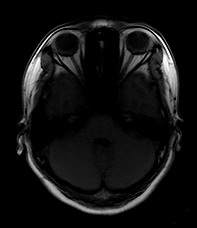

女,46岁,头晕1周。(第四脑室点状高密度灶,ct值约为65hu)。

四脑室脉络从钙化。

第四脑室脉络丛钙化。